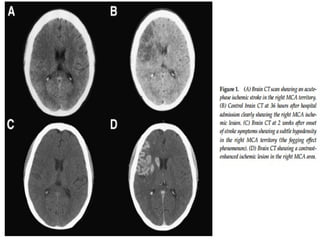

The subset of ischemic stroke is divided into hyperacute,

acute, subacute and chronic stroke based on timing from the

onset of stroke symptoms. It is generally a definition of time

which is the first 6 hours, 6-48 hours, 48h to weeks, and

weeks to months respectively . However such duration does

not have general agreement among various articles

CT FINDINGS

 A. Hyper acute infarct (<6hrs) - Normal (50-60%)

 Hyper dense artery sign(30%)

 Obscuration of the lentiform nuclei

 B . Acute (6-48hrs) - hypodense BG

- Loss of gray white interface along the insula (insular ribbon sign)

- Sulcal effacement

 C. 1 to 3 days - positive Mass effect

Wedge shaped low density area that involve both gray & white

matter. Hemorrhage transformation may occur.

 D. 4 to 7 days - Gyral enhancement on contrast

Mass effect and oedema present

 E. 1 to 8 weeks - Mass effect resolves, fogging of infarct can occur

Contrast enhancement begin to decline but persists for 8-10 weeks

 F. Month to years - Encephalomalacic changes

1-8 weeks

 Contrast enhancement persists.

 Mass effect resolves.

 The swelling starts to subside and the cortex

begins to increase in attenuation. After 2 to 3

weeks following an infarct the cortex regains

near-normal density and imaging at this time

can lead to confusion or missed diagnosis

This is known as the CT fogging phenomenon